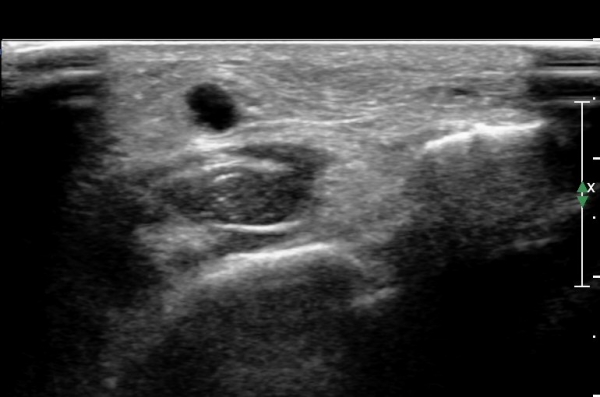

³¶Á¾À» Á¾´Ü¸éÀ¸·Î °üÂûÇÏ´Ï ³¶Á¾ÀÌ ¸»´Ü °æ°ñºñ°ñ°üÀý¿¡¼ À¯·¡µÊÀÌ È®ÀεȴÙ(»çÁø 9).